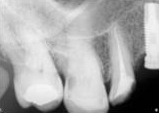

antes depois